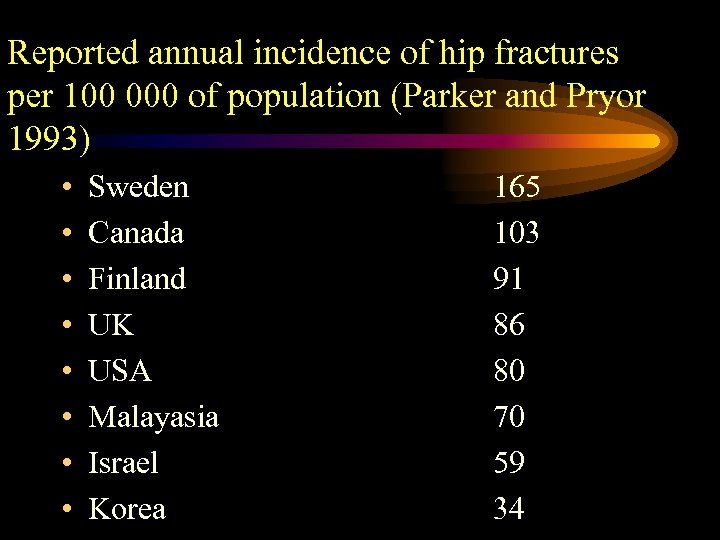

Reported annual incidence of hip fractures per 100 000 of population (Parker and Pryor 1993) • • Sweden Canada Finland UK USA Malayasia Israel Korea 165 103 91 86 80 70 59 34

Reported annual incidence of hip fractures per 100 000 of population (Parker and Pryor 1993) • • Sweden Canada Finland UK USA Malayasia Israel Korea 165 103 91 86 80 70 59 34